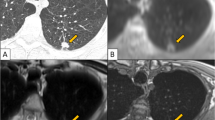

A total of 133/285 lung segments were judged as pathological on the basis of the MRI scans. On the CT examinations—serving as reference standard—pathological changes were detected in 143 /285 lung segments. Thus, 133/143 (93%) of the segmental changes diagnosed by computed tomography were also detected by MRI (Figs. 2, 3).

The third patient with fibrotic sarcoidosis showed scars and subpleural nodules, not clearly visible on MRI (Fig. 4).

Considering all these expected problems, the diagnostic yield of the high-field MRI of the lung in our study was surprisingly good: Of the 143 pathological segments detected by CT, 133 segments were also identified by MRI. The reason for the discrepancy in ten lung segments was not the quality of the MR examination or the presence of artifacts interfering with the evaluation. Rather, the false-negative findings compared with CT were caused by the pathological substrate itself: the lesions missed by MRI were parenchyma scars or small granulomas. Irrespective of the field strength, these are difficult or impossible to detect by MRI because of their low proton density and short relaxation times.

On the other hand, this can also be a diagnostic advantage as this permits differentiation between florid/acute lesions and chronic lesions/scars (Fig. 3) [15–17].